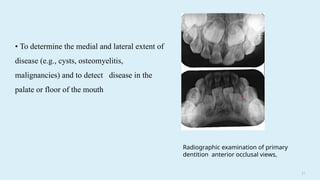

• To determine the medial and lateral extent of

disease (e.g., cysts, osteomyelitis,

malignancies) and to detect disease in the

palate or floor of the mouth

Radiographic examination of primary

dentition anterior occlusal views,